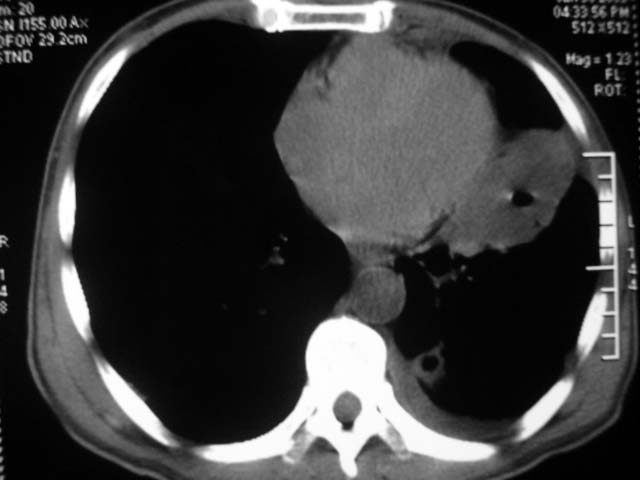

男,52岁,发热2月,糖尿病史。

抗结核治疗irpz方案,血糖未治疗,空腹15.9左右。症状无好转,左胸痛。

复查ct

2、双肺见多发片状及结节状高密度影,大多数病灶中心均见“空泡征”。

3、纵隔内淋巴结肿大。

结果:两肺继发性肺结核并曲霉菌感染。